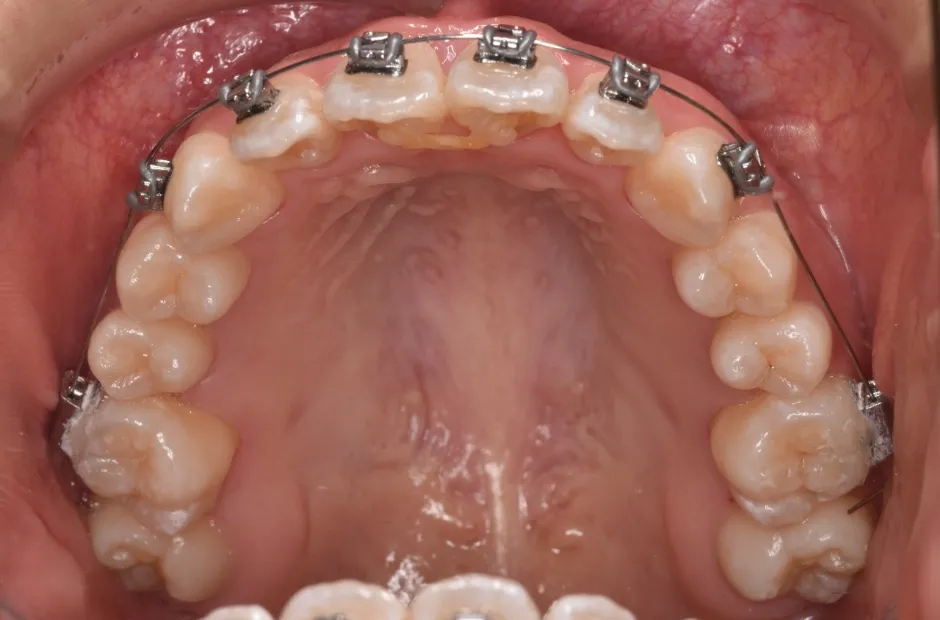

前歯部反対咬合

| 診断名・主訴 | 前歯部反対咬合 |

|---|---|

| 年齢・性別 | 14歳・男性 |

| 治療期間・回数 | 1年2か月 |

| 治療に用いた主な装置 | ブラケット矯正 |

| 抜歯部位 | なし |

| 治療費 | 60万円(税抜) |

| リスク・副作用 | 装置による違和感・疼痛・歯肉退縮・歯根吸収・虫歯のリスクなど |

治療中

治療後